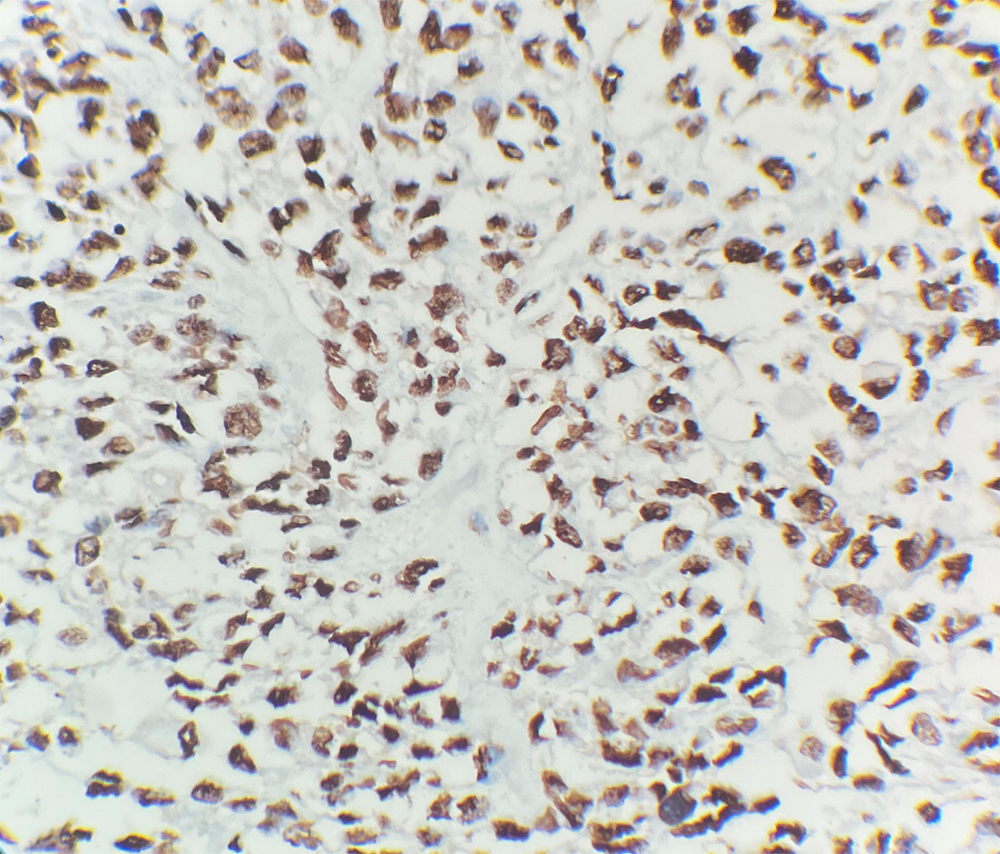

INI-1 Antibody (DA170)

INI-1, also known as SMARCB1, is one of the core subunit proteins of the ATP-dependent SWI/SNF chromatin remodeling complex. It is involved in chromatin remodeling and transcriptional regulation and functions as a tumor suppressor. Nuclear INI-1 expression is seen in virtually all normal human tissues and most malignancies but the INI-1 gene is often mutated or deleted in malignant rhabdoid tumors (MRT), including those arising in the central nervous system, leading to a lack of INI-1 expression.1-3

IHC (FFPE)

Nucleus

Testis